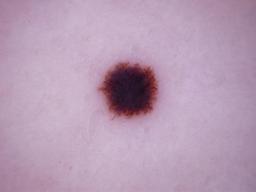

Melanoma and Nevus Dermoscopy Images with Confirmed Histopathological Diagnosis

- Name: Melanoma and Nevus Dermoscopy Images with Confirmed Histopathological Diagnosis

Description:

Collection defined by Dr. Jorge A. Rios-Duarte for a research project.